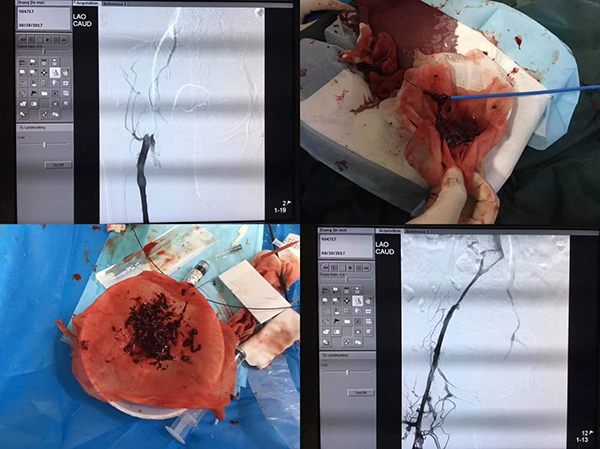

深静脉血栓取栓过程,开通静脉血管

深静脉血栓“看”得见

沧州市人民医院介入医学科付立平主任运用介入技术治疗“轻松”取栓,为患者开通静脉血管。